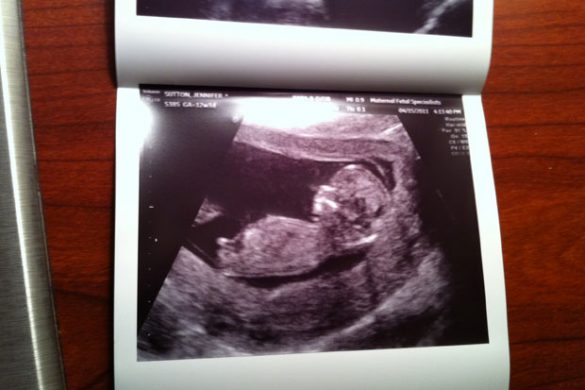

Throughout the beginning pregnancy, it feels like you are constantly looking to that next hurdle to cross. One of the big ones is the fetal nuchal translucency test which is the prime reason for the 12 week ultrasound. The basic premise of the test is to measure the fluid at the back of the babies neck to screen for Downs syndrome. Last Friday, we went in to get that and some preliminary blood work done to test for a host of genetically transmitted things as well.

For some reason, I thought we were actually getting one of those 3D ultrasounds done, but…as it turns out…it was just your regular, run of the mill ultrasound. At first, I was a little bit disappointed, but then I remembered a conversation my wife and I had about the 3D ultrasounds. From the pictures we have seen, they look kind of weird! It is almost like we really are not supposed to see our babies that clear at this point in life. Once it is born…we will get to see it for the rest of it’s life in 3D anyway…so I focused on what we were there for and we got things rolling.

Seeing Your Baby As A Moving Human

When they first put your baby on the screen at 12 weeks (we were around 13 at the time), there was an incredible shock affect. This entire time, I knew there is a baby growing inside my wife, but it really doesn’t hit home until you see arms, legs, head, fingers and other real body parts for the first time. It really looks like a small human now! Our little one sat all nice and still while the tech took all of the measurements and everything looked great. After she was done, it was almost as if our baby knew “Hey! My job is done!” and it started twisting and moving all over the place! It really was crazy to watch and we found ourselves in a very quiet and peaceful ultrasound room as we got to watch our baby interact with its environment for the first time.

The tech then went on to take pictures of the legs, arms and brain. I made the typical new dad comment…”Look! A big brain just like dad’s!”. I am pretty sure I am not the first one to throw that comment out there and it completely backfired at checkout when I said something stupid and the nurse said…”Big brain like dad’s right?!” My wife loved it. It’s all good though…it’s my job to embarrass her anyway. The truth is…as a husband of a very intelligent, beautiful and driven wife, I hope our baby gets a lot of the characteristics that make her the incredible person she is.